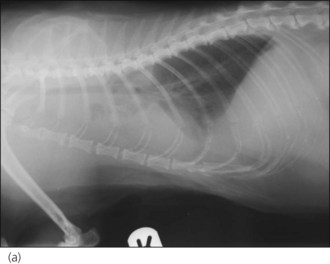

In the author’s experience, neoplasia and congestive heart failure (see Ch. 31) are the two most common causes identified in cats (see Figures 32.1-32.4).

image image image image

Figure 32.4 Right lateral and dorsoventral thoracic radiographs of a cat with idiopathic chylothorax (a, b) before and (c, d) after thoracocentesis. The post-drainage films were taken the day after under general anaesthesia; an oesophageal stethoscope is visible.